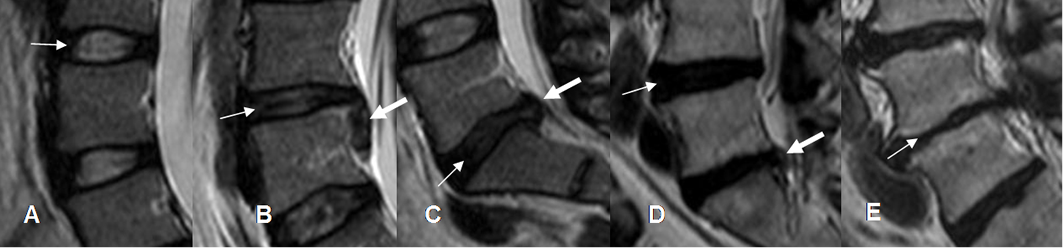

Fig 113. Tipos de degeneración del disco.

A: RM axial en T2. Disco con diferenciación entre el núcleo pulposo y el anillo fibroso.

B: RM axial en T2. Disminución en la señal del núcleo pulposo, persistiendo banda hipointensa central.

C: RM axial en T2. Zona central del disco con señal intermedia.

D: RM axial en T2. Disco hipointenso, sin poder diferenciar el núcleo pulposo del anillo fibroso.

E: RM axial en T2. Disco hipointenso, con pérdida del espacio.

En B existe una hernia extruida y en C y D, una hernia central.